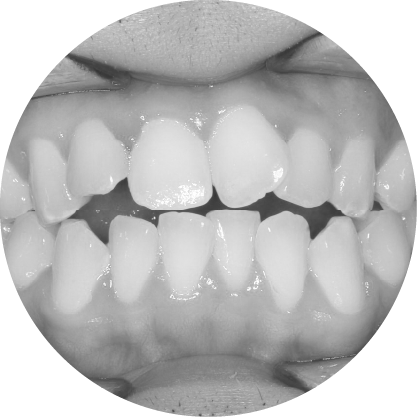

ช่องว่างระหว่างฟัน (Diastema)

การปิดช่องว่างระหว่างฟัน เพื่อรอยยิ้มที่สมบูรณ์แบบ

"ช่องว่างระหว่างฟันหรือไดแอสเทมา หมายถึงช่องว่างระหว่างฟันที่เห็นได้ชัด ซึ่งอาจเป็นปัญหาทางความงามสำหรับหลายๆ คนการจัดฟันสามารถปิดช่องว่าง เหล่านี้ได้อย่างมีประสิทธิภาพทำให้มีรอยยิ้มที่สม่ำเสมอและสวยงาม"

ตัวอย่างในชีวิตจริง